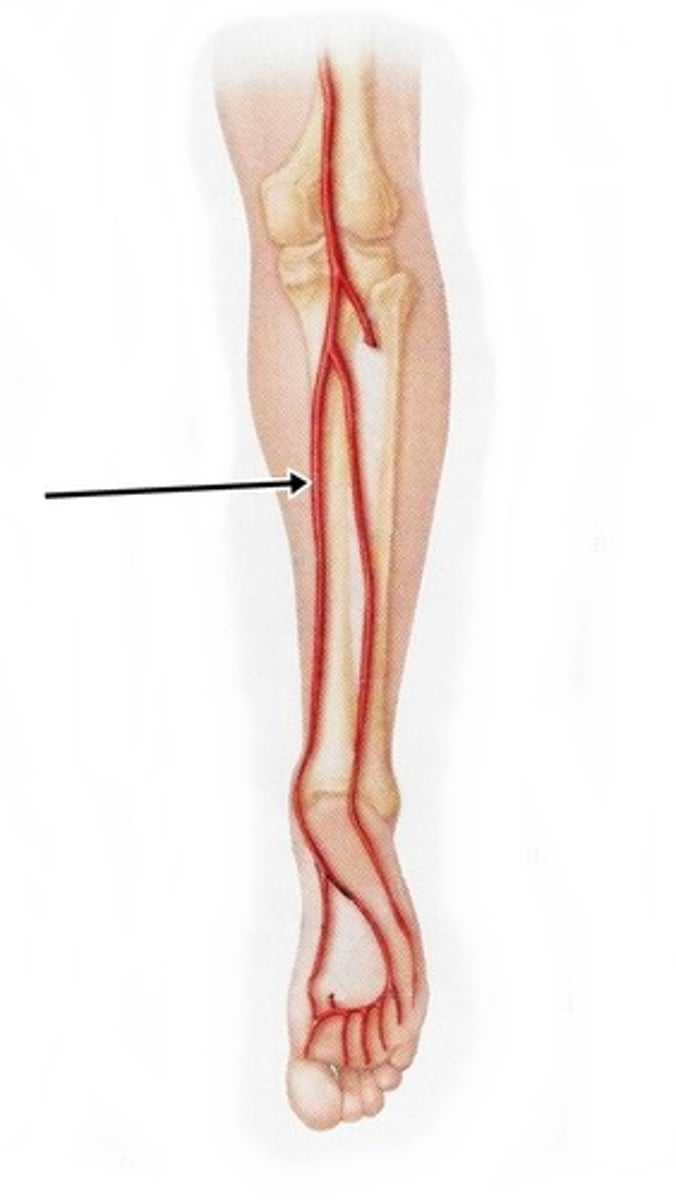

popliteal artery

feeds the posterior tibial artery, fibular artery, anterior tibial artery, and dorsalis pedis artery

anterior tibial artery

serves the muscles in the anterior compartment of the leg

posterior tibial artery

serves the muscles in the posteromedial part of the leg